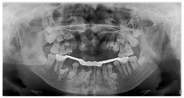

,反覆盖10mm,双侧尖牙及磨牙近中关系;51、61扭转,上颌牙弓狭窄,腭盖高拱,31、41间可见间隙约5mm(图2)。(3)影像学检查:①曲面断层片示多数乳牙滞留,恒牙迟萌,多颗埋伏阻生多生牙。54、64远中邻面低密度影及髓,牙根吸收(图3);②CBCT示全口恒牙排列紊乱,上下颌骨内可见13颗多生牙,均位于恒牙胚舌腭侧,形态类似相邻恒牙胚(图4);③头颅侧位片示头颅侧位片示上颌骨发育不足(NA-Apo:-5.9°),下颌前突(SNB: 98.2°;FH-NPo:90.0°),骨性III类错

畸形(ANB:-5.1°;FMA:31.0°)(图5)(表1);④头颅正位片示颅缝轻微增宽;⑤胸片示双侧锁骨远心端发育不足(图6)。